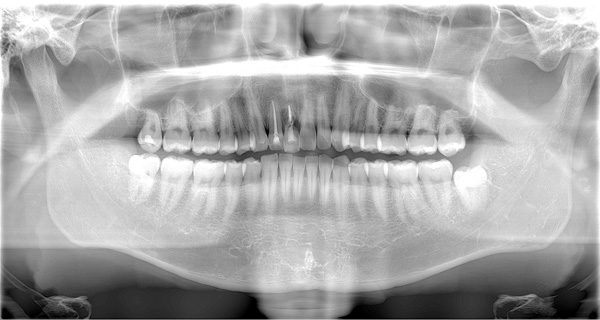

| 年代・性別 | 50代 女性 |

|---|---|

| 主訴 | 左上のブリッジがグラグラして外れそう |

| 治療期間 | 約18ヶ月 |

| 費用 | 1,600,000円 |

| 治療内容 | インプラント、骨造成、サイナスリフト、セラミック修復 |

| 治療に伴うリスク | インプラント周囲炎 セラミックの破折、脱離 |